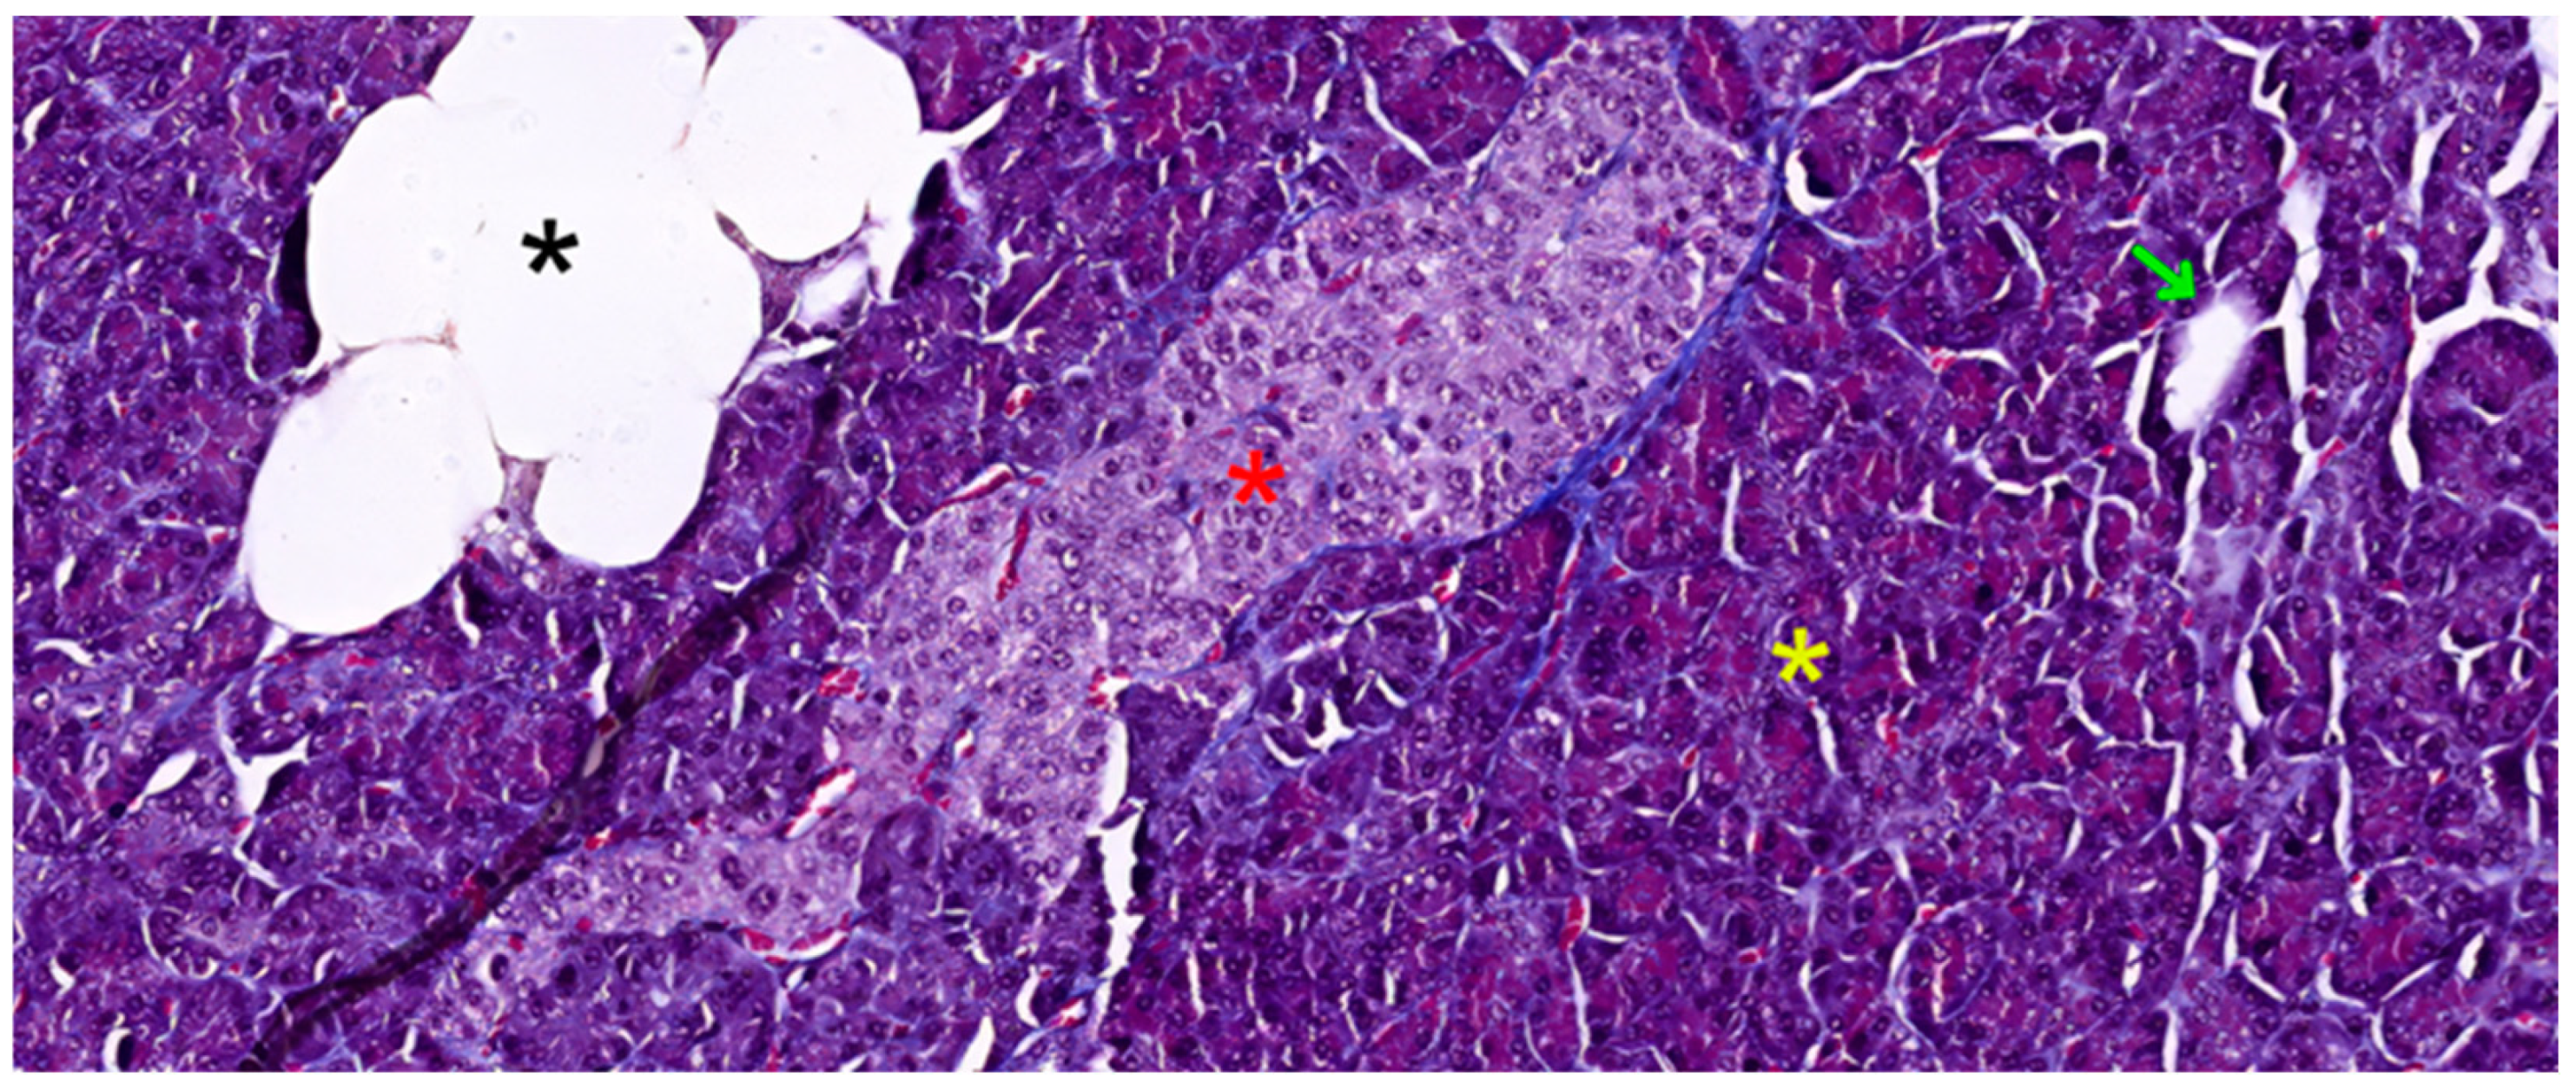

5. Histopathology of Acute Pancreatitis